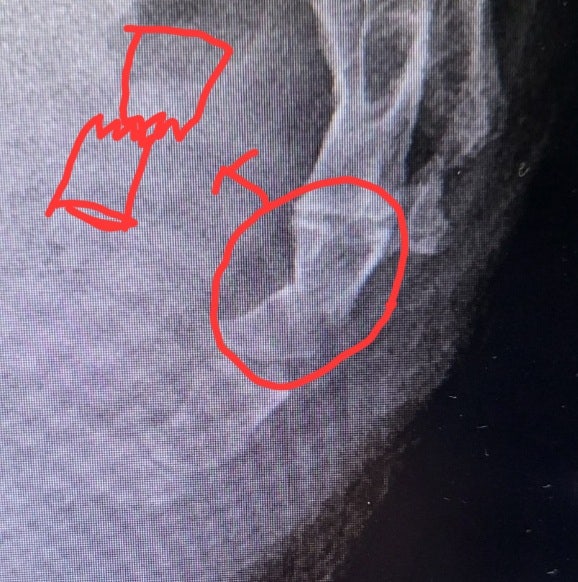

꼬리뼈 부러진 후기 마지막 일기(회복과정)

2023. 9월 24일 꼬리뼈가 부러지고 발목을 접지른 사건 이후.... 한달 쯤 이후 2022. 10월24일 (생각해보니...

꼬리뼈 골절(+삔.. 접지른 다리) 후기 및 치유 과정.

아무래도 이제 다시는 이런 경험을 하지말자는 의미 + 다른 사람들도 이런 상황이 생겼을때 알고는 있자는 ...